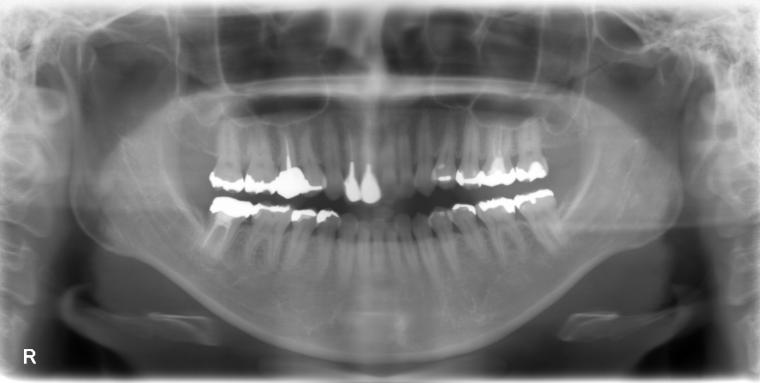

BEFORE

53歳女性/上1本欠損/インプラント埋込手術

前歯の詰め物が割れたかもしれないの主訴でご来院された方です。

保存状態が厳しかった為、上顎側切歯の抜歯となりました。

抜歯後に土台となる骨を作る処置の後、インプラントを1本埋入しました。